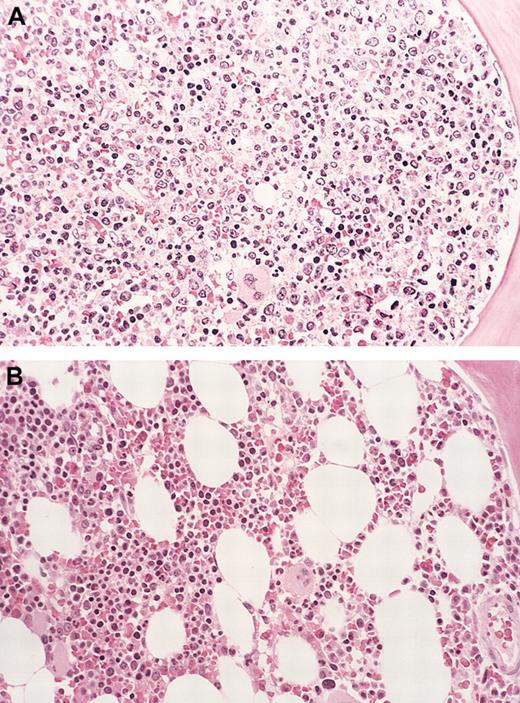

Bone marrow eosinophil cytoreduction with imatinib therapy (case 6).

Hematoxylin-eosin (H&E)–stained bone marrow biopsy tissue (A), showing markedly hypercellular marrow with left-shifted granulopoiesis and eosinophilia before treatment with imatinib. (B) Shows the dramatic reduction in marrow cellularity with normal trilineage hematopoiesis after imatinib therapy (at 16 weeks). Original magnification for both panels, × 160.

The patient had a dramatic response to therapy that was manifest both clinically, and by decreasing eosinophilia, within a week of starting treatment. At re-evaluation (12 weeks), the patient was clinically asymptomatic and reported a dramatic increase in his energy level and stamina. He had gained 9 kg in weight, and the spleen tip was no longer convincingly palpable on physical examination. Laboratory testing revealed improved hemoglobin concentration and platelet count, as well as complete resolution of the eosinophilia and leukoerythroblastic picture (Table 1). A follow-up bone marrow examination revealed a dramatic decrease in overall cellularity and resolution of eosinophilia (Figure 2). The patient at last follow-up continued to be in clinical and histologic remission.